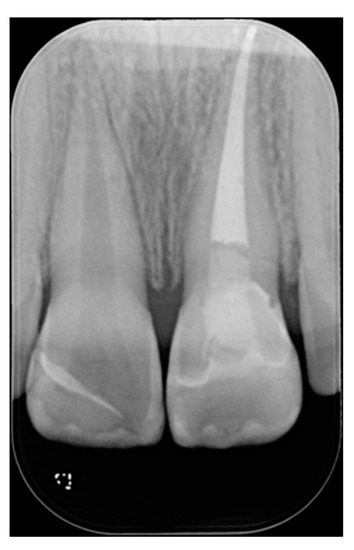

A healthy 10-year boy presented to the dental office after traumatic accident during sport activity. Upper central incisor presented horizontal fracture with no pulp exposure (Figure 1 and Figure 2). Tooth fragment was not retrieved after the traumatic accident. The tooth responded positively to pulp tests (cold and electrical). In order to manage sensitivity and protect the tooth before the restoration appointment, after rubber dam placement, a universal adhesive (Clearfil Universal Bond Quick, Kuraray Noritake Dental, Tokyo, Japan) was applied in self-etch mode followed by a little layer (approximatively 0.5 mm) of flowable composite (Clearfil Majesty ES Flow, A2, Kuraray Noritake Dental, Tokyo, Japan). A silicone impression (Imprint, 3M ESPE, St. Paul, MN, USA) was therefore taken in order to develop a wax-up (Figure 3) and a palatal silicone index (Elite HD+, Zhermack, Badia Polesine, Italy).

Figure 1.

Initial clinical situation. Reprinted from Restauri diretti nei settori anteriori, G. Paolone, S. Scolavino, © 2021, with permission from Quintessence Publishing Italy.

Figure 2.

Initial x-ray. Reprinted from Restauri diretti nei settori anteriori, G. Paolone, S. Scolavino, © 2021, with permission from Quintessence Publishing Italy.